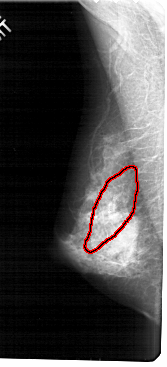

A_1932_1.LEFT_CC

FILE: A_1932_1.LEFT_CC.OVERLAY

TOTAL_ABNORMALITIES 1

ABNORMALITY 1

LESION_TYPE CALCIFICATION TYPE PLEOMORPHIC DISTRIBUTION SEGMENTAL

ASSESSMENT 5

SUBTLETY 4

PATHOLOGY MALIGNANT

TOTAL_OUTLINES 1

BOUNDARY